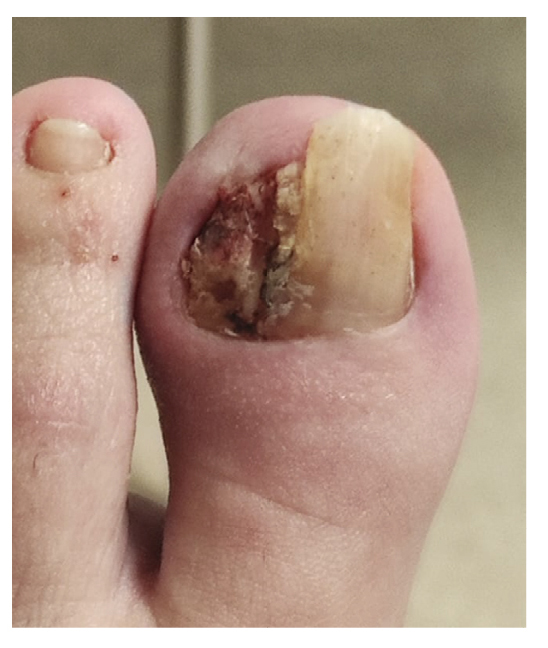

La paciente refiere proceso de inicial de onicocriptosis de 7 meses de evolución (septiembre de 2022), en el borde medial del primer dedo del pie izquierdo, con la presencia de tejido de granulación ungueal en dicho borde, el cual le produce dolor e inflamación digital (Figura 1). La paciente recibe tratamiento por su podólogo que consiste en quiropodia y limpieza del canal; se pautan posteriormente curas diarias con mupirocina para la lesión. Existe mala evolución de la lesión en los días siguientes con aumento de dolor y sensibilidad al tacto. Se modifica el tratamiento pautando amoxicilina/ácido clavulánico 875/125 mg, 1/8 h junto con el uso de analgésicos orales (Figura 2). La paciente continúa con mala evolución sintomatológica y acude a su centro de salud donde se realiza radiografía con la cual se descarta la presencia de infección profunda (osteomielitis).

Figura 1. Proceso inicial de onicocriptosis y granuloma reactivo.

Figura 2. Progresión clínica tras tratamiento ATB y analgésico.